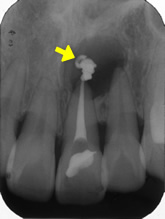

感染根管処置症例.2

主訴:前歯に違和感がある。

- 過去に根管治療を行っていたが、感染を起こし根の先に大きな膿の袋が出来ている。

- 再度根管治療を行い、根の内部から膿の袋に直接薬を作用させている。

- 根管充填剤が根尖(根の先端)まできっちりと充填されている。術前に存在した大きな膿の袋は消失してきている。